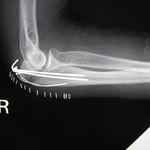

○右橈骨尺骨骨折

中学生 野球プレー中、走塁者と衝突し受傷しました。

救急病院で検査し骨の転移(ずれ)があったので牽引(引っ張ってもとにもどす操作)し整復しました。

固定は二の腕から指先まで固定し手首は、かなり手のひら側に曲げられた状態でした。本人は圧迫感と痒みがあり、日常の衣服の着替えがかなり制限され母親と相談に来られました。

本来は柔道整復師が独断で処置を変更できないため、信頼できる整形外科医に依頼し骨折の状態を確認、今後の治療に同意してもらいました。

当院では肘を開放して、手首も鉛筆が握れる固定にしました。毎日来院してもらい局所に超音波療法と浮腫を取るための軽いマッサージ、指や肘の曲げ伸ばしをしました。

治療後は腕を清潔にして新しいネットと包帯で再度固定するので痒みやストレスから解放されます。二週間後は、骨折した部位の圧痛も消え手首もかなり自動運動できるようになりました。脅威の回復力です。

肘から手首までのギプス→肘から手首の固定に変更→二週間折れた所の圧痛消失→さらに半分の固定

毎日皮膚を清潔にして包帯交換をするので、ストレスを軽減と痒みから解放されます